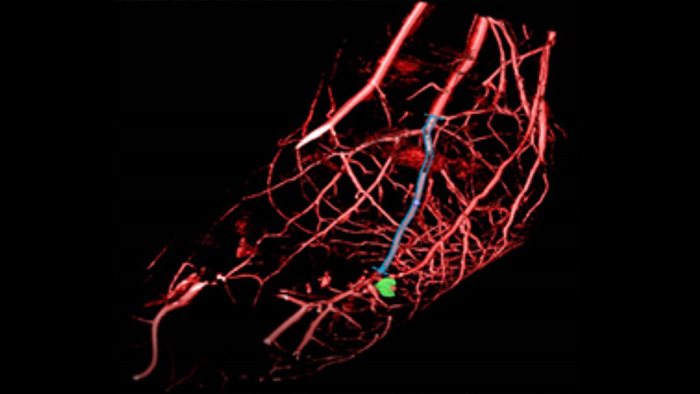

XperGuide offers live 3D image needle guidance, letting you bring percutaneous needle procedures into the Hybrid OR. It overlays live fluoroscopy and 3D soft tissue imaging data from previously acquired CT or MR scans or Philips XperCT, providing information on the needle path and target.